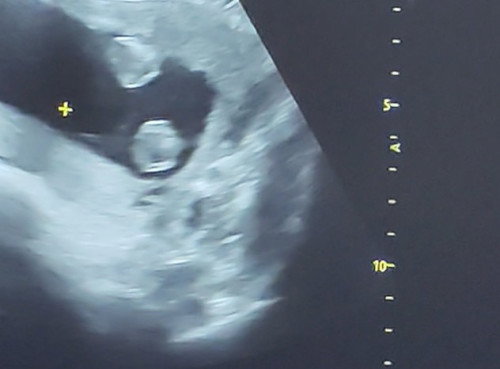

Nagpagender ako khapon 19wks na sabi babae pero nkadapa kasi c baby at diko din nkita yung genital pwede kayang mali ang sonologist my alam ba kyo na nagkamali na ang sono? Thanks panganay ko kc bby girl na sana itong bunso boy naman kasi CS ako hirap manganak high risk pa. Thanks po sa sasagot. #19_weeks1day